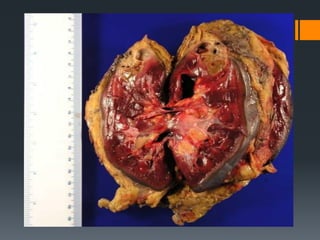

Renal Failure : When the kidney ceases

functioning

Common Disorders Associated withthe Urinary System Renal Failure : When the kidney ceases functioning